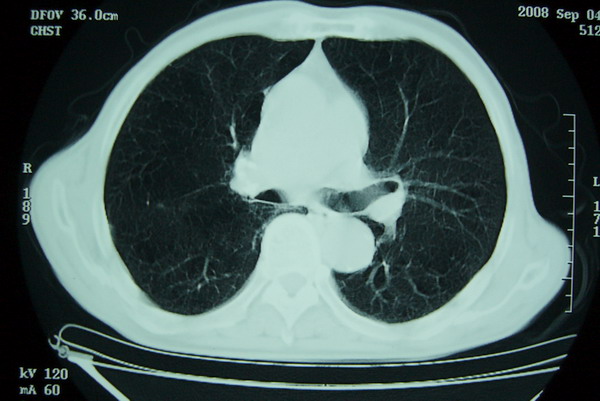

标题: CT15579:男 86岁 咳嗽 咳少量白痰 发热2天 吸烟史60年 [打印本页]

标题: CT15579:男 86岁 咳嗽 咳少量白痰 发热2天 吸烟史60年

右上肺一不规则团块,边缘有分叶和毛刺,纵隔有淋巴结肿大。右肺周围性肺癌首先考虑。